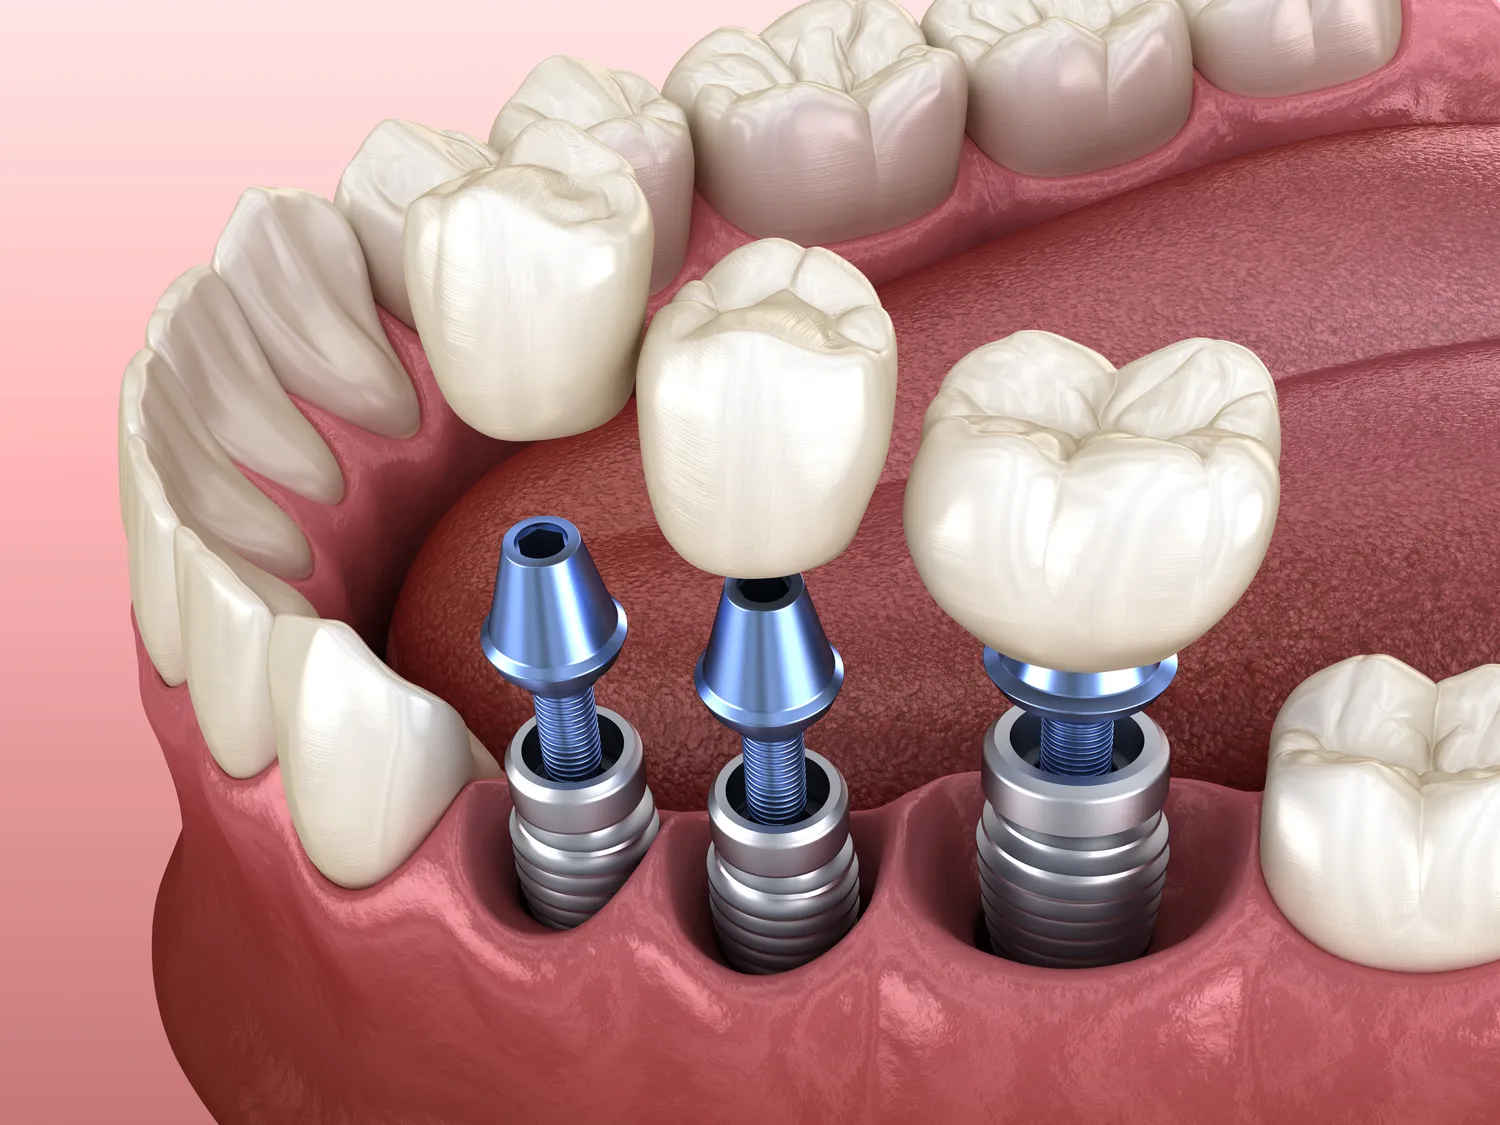

Implanty to sztuczne struktury, które są wszczepiane w organizm w celu zastąpienia brakujących zębów lub innych elementów anatomicznych. W przypadku implantów stomatologicznych, ich głównym celem jest odbudowa funkcji żucia oraz estetyki uśmiechu. Proces wszczepiania implantu polega na umieszczeniu tytanowego słupa w kości szczęki lub żuchwy, który następnie integruje się z tkanką kostną. Dzięki tej integracji implant staje się stabilnym fundamentem dla korony zęba, mostu lub protezy. Warto zaznaczyć, że implanty są projektowane tak, aby były biokompatybilne, co oznacza, że nie wywołują reakcji alergicznych ani odrzucenia przez organizm. Po zakończeniu procesu gojenia, pacjent może cieszyć się pełną funkcjonalnością zęba, a także poprawionym wyglądem.

Na rynku dostępnych jest kilka rodzajów implantów, które różnią się między sobą materiałem wykonania, kształtem oraz przeznaczeniem. Najpopularniejsze są implanty tytanowe, które charakteryzują się wysoką wytrzymałością oraz doskonałą biokompatybilnością. Istnieją również implanty ceramiczne, które są bardziej estetyczne i często wybierane przez pacjentów z alergiami na metale. W zależności od potrzeb pacjenta można stosować różne typy implantów, takie jak implanty jednoetapowe, które są wszczepiane w jednym zabiegu, czy też implanty dwuetapowe, które wymagają wcześniejszego gojenia kości przed umieszczeniem korony. Ponadto istnieją także implanty miniaturowe, które znajdują zastosowanie w sytuacjach ograniczonej ilości kości lub jako tymczasowe rozwiązanie.

Proces zakupu i wszczepienia implantu rozpoczyna się od wizyty u stomatologa specjalizującego się w implantologii. Lekarz przeprowadza szczegółowy wywiad medyczny oraz wykonuje badania diagnostyczne, takie jak zdjęcia rentgenowskie czy tomografia komputerowa, aby ocenić stan kości i określić najlepszą lokalizację dla implantu. Po ustaleniu planu leczenia pacjent otrzymuje informacje na temat kosztów oraz czasu trwania całego procesu. Następnie następuje etap wszczepienia implantu, który odbywa się w znieczuleniu miejscowym lub ogólnym w zależności od skomplikowania zabiegu. Po wszczepieniu implantu konieczne jest okresowe monitorowanie gojenia oraz integracji z kością. W tym czasie pacjent może otrzymać tymczasową koronę lub protezę do momentu zakończenia procesu gojenia. Po kilku miesiącach następuje odsłonięcie implantu i umieszczenie stałej korony lub innego uzupełnienia protetycznego.